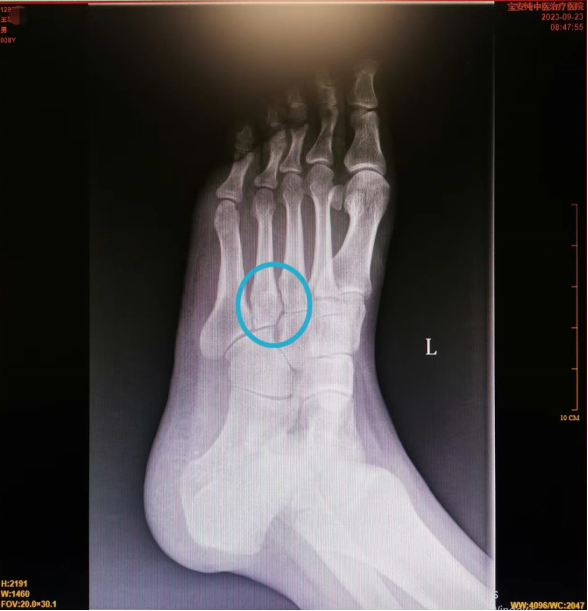

辅助检查:2023-09-23我院右侧足部正斜位片:左足第3跖骨体、第4跖骨基底部骨质密度不均,内见线状影周围骨质密度增高,余足部诸骨骨质未见异常。 考虑左足第3、4跖骨陈旧性骨折,请结合临床病史。

诊断:1、左第3跖骨体陈旧性骨折 2、左第4跖骨基底部陈旧性骨折

本病例疑惑的就是第一次拍片竟然没发现骨折,考虑可能骨折线隐匿或拍摄片子时忘了拍斜位片,因为正位片上确实很难发现骨折。而没有明确诊断,导致患者没有适当休息、制动,导致3月后仍可见骨折线存在,耽误了病情。